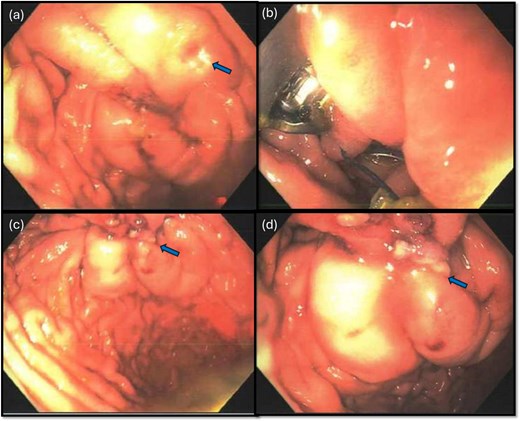

Laparoscopy began with placement of a 5 mm umbilical trocar and two additional 5 mm trocars in the right and left abdomen. Turbid fluid was encountered and suctioned. In the upper-abdomen, significant inflammatory omental adhesions were found against the right upper quadrant and gallbladder. A complex fluid collection with inflammation was identified in the left upper quadrant (Fig. 2). These inflammatory adhesions were carefully dissected using a Cool-SealTM device to visualize the pylorus and duodenum; however, inflammation around the gallbladder prevented full release of these adhesions. Mobilization of the gastrocolic ligament revealed a normal posterior gastric wall. Because inflammatory exudates obscured the anterior stomach and the first and second part of the duodenum, making the perforation’s origin (duodenal or gastric) initially unclear, simultaneous intraoperative-endoscopy was requested for precise localization.

Intraoperative pictures demonstrating the sequelae of the hollow viscus perforation. The pictures in (a) and (b) demonstrate contamination and associated inflammatory adhesions in the left and right upper quadrant, respectively. The pictures in (c) and (d) demonstrate the antral perforation. The tip of the Maryland dissector was able to insert into the perforation (d) to assist with identification of the perforation endoscopically for closure.

The gastroenterology team performed concurrent endoscopy using. With air insufflation and transillumination, a small pinpoint perforation was clearly identified on the anterior surface of the gastric-antrum (Figs 2 and 3).

To aid endoscopic visualization of the small perforation, a Maryland grasper was gently inserted into it (Fig. 2); the grasper’s tip, visualized endoscopically, confirmed the exact location. The remainder of the esophagus, stomach, and duodenum appeared normal. The Overstitch™ endoscopic-suturing device, mounted on a double-channel therapeutic endoscope and utilizing a tissue-helix for full-thickness bites, was used. Three full-thickness inverted figure-of-eight 2–0 Prolene sutures were placed at the perforation. Laparoscopic visualization confirmed full-thickness suture placement before the sutures were cinched, effectively closing the gastric wall defect (Fig. 3).